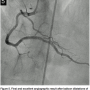

the RCA in the same setting. Surprisingly, the stent in the RCA showed a severe, subclinical, and possibly ongoing ST with a particularly speckled appearance (Figures 1A and 1B). This image persisted despite nitroglycerin administration with coronary flow of TIMI II. Following this unexpected finding, a ChoICE PT wire (Boston Scientific, Natick, Massachusetts) was advanced across the stent into the distal posterior descending coronary artery. OCT imaging (DragonFly catheter and C7XR system, LightLab

Imaging) was then performed, showing a “cheese-like” or “spider web-like” structure composed of highly reflective material throughout the stent (Figures 2A–2C). This “spider web-like” occlusive thrombus did not induce shadowing of distal structures and stent expansion could be readily identified. Moderate underexpansion (expansion of 76%) of its distal segment was recognized (measured as the ratio of minimal stent cross-sectional area divided by the mean of proximal and distal reference lumen areas). However, strut malapposition was not detected. Then, an aspiration catheter (ExportAP, Medtronic) was successfully used with improvement of coronary blood flow after retrieval of a large amount of a distinct “white” thrombotic material (Figures 3A and 3B). Finally, the stent was postdilated with a 3.5 x 14 mm Mercury balloon (Abbott Vascular, Abbott Park, Illinois) at 18 atmospheres. Postdilation, OCT showed improved expansion of the stent (stent expansion of 95%) and marked reduction of the thrombotic load, although some persistent thrombus lining apposed to the stent struts was evident (Figures 4A and 4B). An excellent angiographic result with a TIMI III coronary flow was eventually obtained, with mild transient flow deterioration of the posterolateral branch (Figure 5). Clinical course was uneventful and no rise in cardiac markers was detected.

- The angiographic “speckled” appearance (Figures 1A and 1B) that persisted after nitroglycerin administration previously reported by our group as linked to a recent event;11

In our patient, OCT examination provided details on the characteristics of the evolving thrombus that showed a pattern formed by multiple tracts of low backscattering protrusions without significant dorsal shadow, suggestive of an ongoing organization of white thrombus. This was confirmed by the histopathology of the material obtained by thromboaspiration. Previous reports have emphasized the unique value of OCT to differentiate red thrombus (with shadowing of distal structures) from white thrombus (without distal shadowing).10 Furthermore, although stent expansion was adequate by angiographic criteria, clear underexpansion and asymmetry of the stent was detected by OCT. Otake et al13 previously showed that underexpansion of sirolimus-eluting stents on OCT could be an important factor in thrombus formation. In the present case, a speckled angiographic pattern and spider web-like projections of white thrombus on OCT, suggestive of either an evolving stent thrombosis or an occlusion-recanalization process, was readily identified. In our previous description of an asymptomatic patient experiencing ongoing stent thrombosis, we found a similar speckled angiographic appearance at the stent site, and a soft, hypoechogenic and obstructive thrombus on IVUS.11 At that time, however, OCT was not available and we failed to fully characterize the pattern of the evolving stent thrombosis. In our current patient, OCT enabled us to recognize a distinct thrombus with cheese-like or spider web-like appearance that suggested a unique phenomenon occurring within the stent. Accordingly, it is tempting to speculate that ST does not occur as a result of a confined, localized, and parietal thrombus lining that increases in size and eventually occludes the stent, but rather from spider web-like thrombus (accounting for the speckled angiographic pattern), initially encompassing only a segment of the stent, but allowing a TIMI III coronary flow, and eventually progressing with obliteration of residual channels and leading to vessel closure.